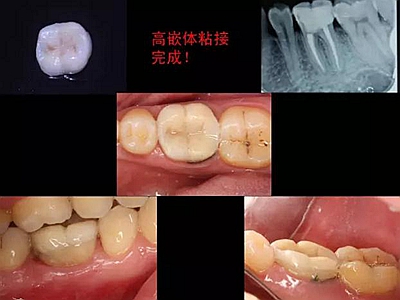

一周后拆除縫線,試戴高嵌體,試戴合適后雙固化粘結。調(diào)合,拋光。

冠延長手術和高嵌體修復,本來需要很多次復診的患者,兩次就診,就把患者難以處理的問題輕松解決了。減少了患者的就診次數(shù)和時間。

最后附幾例一次性根管治療+冠延長手術+高嵌體修復的病例,均為兩次完成。第一次就診:根管治療一次完成,后冠延長手術,然后高嵌體預備,取模,第二次就診,拆線,試戴嵌體。具體在此不做詳細說明,圖中有詳解。

最后附昨天備牙,今日戴牙的一個美塑嵌體。